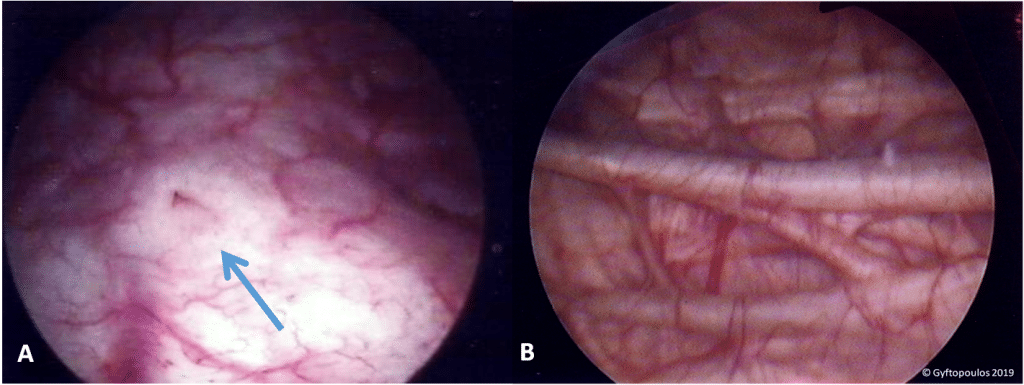

The bladder is an organ of the urinary system. It plays two main roles: Temporary storage of urine – the bladder is a hollow organ with distensible walls. It has a folded internal lining (known as rugae), which allows it to accommodate up to 400-600ml of urine in healthy adults. Assists in the expulsion of urine – the musculature of the bladder contracts during micturition, with concomitant relaxation of the sphincters. In this article, we shall look at the anatomy of the bladder – its shape, vasculature and neurological control. By TeachMeSeries Ltd (2025) Fig 1Overview of the urinary tract. Pro Feature - 3D Model You've Discovered a Pro Feature Access our 3D Model Library Explore, cut, dissect, annotate and manipulate our 3D models to visualise anatomy in a dynamic, interactive way. Learn More Shape of the Bladder The appearance of the bladder varies depending on the amount of urine stored. When full, it exhibits an oval shape, and when empty it is flattened by the overlying bowel. The external features of the bladder are: Apex – located superiorly, pointing towards the pubic symphysis. It is connected to the umbilicus by the median umbilical ligament (a remnant of the urachus). Body – main part of the bladder, located between the apex and the fundus Fundus (or base) – located posteriorly. It is triangular-shaped, with the tip of the triangle pointing backwards. Neck – formed by the convergence of the fundus and the two inferolateral surfaces. It is continuous with the urethra. Urine enters the bladder through the left and right ureters, and exits via the urethra. Internally, these orifices are marked by the trigone – a triangular area located within the fundus. In contrast to the rest of the internal bladder, the trigone has smooth walls (this is explained by the different embryological origin: the trigone is developed by the integration of two mesonephric ducts at the base of the bladder). Myrto @ PatrasAnatomy Fig 2Anatomical features of the bladder. Musculature The musculature of the bladder plays a key role in the storage and emptying of urine. In order to contract during micturition, the bladder wall contains specialised smooth muscle – known as detrusor muscle. Its fibres are orientated in multiple directions, thus retaining structural integrity when stretched. It receives innervation from both the sympathetic and parasympathetic nervous systems. The fibres of the detrusor muscle often become hypertrophic (presenting as prominent trabeculae) in order to compensate for increased workload of the bladder emptying. This is very common in conditions that obstruct the urine outflow such as benign prostatic hyperplasia. There are also two muscular sphincters located in the urethra: Internal urethral sphincter: Male – consists of circular smooth fibres, which are under autonomic control. It is thought to prevent seminal regurgitation during ejaculation. Females – thought to be a functional sphincter (i.e. no sphincteric muscle present). It is formed by the anatomy of the bladder neck and proximal urethra. External urethral sphincter – has the same structure in both sexes. It is skeletal muscle, and under voluntary control. However, in males the external sphincteric mechanism is more complex, as it correlates with fibres of the rectourethralis muscle and the levator ani muscle. Kostis Gyftopoulos MD, PhD Fig 3Endoscopic view of the bladder. (A) The trigone and right ureteric orifice. (B) Prominent trabeculae of the bladder wall (hypertrophic fibres of the detrusor muscle). Pro Feature - Dissection Images Sagittal section of the female pelvis. Sagittal section of the female pelvis. You've Discovered a Pro Feature Access our Dissection Image Library Enhance your understanding with high-resolution dissection images showcasing real-life anatomy. Learn More Vasculature The vasculature of the bladder is primarily derived from the internal iliac vessels. Arterial supply is via the superior vesical branch of the internal iliac artery. In males, this is supplemented by the inferior vesical artery, and in females by the vaginal arteries. In both sexes, the obturator and inferior gluteal arteries may also contribute small branches. Venous drainage is achieved by the vesical venous plexus, which empties into the internal iliac veins. The vesical plexus in males is in continuity at the retropubic space with the prostate venous plexus (plexus of Santorini), which also receives blood from the dorsal vein of the penis By TeachMeSeries Ltd (2025) Fig 4Arterial supply to the bladder via the superior vesical arteries. Lymphatics The superolateral aspect of the bladder drains into the external iliac lymph nodes. The neck and fundus drain into the internal iliac, sacral and common iliac nodes. Nervous Supply Neurological control is complex, with the bladder receiving input from both the autonomic (sympathetic and parasympathetic) and somatic arms of the nervous system: Sympathetic – hypogastric nerve (T12 – L2). It causes relaxation of the detrusor muscle, promoting urine retention. Parasympathetic – pelvic nerve (S2-S4). Increased signals from this nerve causes contraction of the detrusor muscle, stimulating micturition. Somatic – pudendal nerve (S2-4). It innervates the external urethral sphincter, providing voluntary control over micturition. In addition to the efferent nerves supplying the bladder, there are sensory (afferent) nerves that report to the brain. They are found in the bladder wall and signal the need to urinate when the bladder becomes full. The Bladder Stretch Reflex The bladder stretch reflex is a primitive spinal reflex, in which micturition is stimulated in response to stretch of the bladder wall. It is analogous to a muscle spinal reflex, such as the patella reflex. During toilet training in infants, this spinal reflex is overridden by the higher centres of the brain, to give voluntary control over micturition. The reflex arc: Bladder fills with urine, and the bladder walls stretch. Sensory nerves detect stretch and transmit this information to the spinal cord. Interneurons within the spinal cord relay the signal to the parasympathetic efferents (the pelvic nerve). The pelvic nerve acts to contract the detrusor muscle, and stimulate micturition. Although it is non-functional post childhood, the bladder stretch reflex needs to be considered in spinal injuries (where the descending inhibition cannot reach the bladder), and in neurodegenerative diseases (where the brain is unable to generate inhibition). Clinical Relevance Spinal Cord Injuries and the Bladder The bladder has important clinical considerations when it comes to spinal cord lesions. There are two different clinical syndromes, depending on where the damage has occurred. Reflex Bladder – Spinal Cord Transection Above T12 In this case, the afferent signals from the bladder wall are unable to reach the brain, and the patient will have no awareness of bladder filling. There is also no descending control over the external urethral sphincter, and it is constantly relaxed. There is a functioning spinal reflex, where the parasympathetic system initiates detrusor contraction in response to bladder wall stretch. Thus, the bladder automatically empties as it fills – known as the reflex bladder. Flaccid Bladder – Spinal Cord Transection Below T12 A spinal cord transection at this level will have damaged the parasympathetic outflow to the bladder. The detrusor muscle will be paralysed, unable to contract. The spinal reflex does not function. In this scenario, the bladder will fill uncontrollably, becoming abnormally distended until overflow incontinence occurs. Clinical Relevance Urine Retention Besides neurogenic dysfunction of the bladder, normal bladder emptying may be hampered by any form of obstruction, from the level of the bladder neck downwards. In males, the most common cause is obstruction due to prostate enlargement (BPH). Other causes include obstruction by a stone or large blood clot. Acute retention is a medical emergency, as the bladder has a “normal” functional capacity with is pushed to the limit due to accumulation of urine in an acutely obstructed reservoir. The patient feels increasingly excruciating pain and the placement of a urinary catheter alleviates the symptoms immediately. Chronic retention is a gradual procedure due to incomplete obstruction of the urine outflow. This leads to accumulation of residual urine in the bladder through months or even years; the bladder is therefore progressively distended in volumes that exceed 1-1.5 lt of urine. Chronic retention is often accompanied by impairment of renal function. However no pain is usually present as the bladder is gradually stretched. Chronic retention of urine is often complicated by infections and formation of bladder stones due to urine stasis and accumulation of minerals in the urine Kostis Gyftopoulos MD, PhD Fig 4Endoscopic view of stones in the bladder. Do you think you’re ready? Take the quiz below Pro Feature - Quiz The Urinary Bladder Question 1 of 3 Submitting... Skip Next Rate question: You scored 0% Skipped: 0/3 1800 More Questions Available Upgrade to TeachMeAnatomy Pro Challenge yourself with over 1800 multiple-choice questions to reinforce learning Learn More Rate This Article